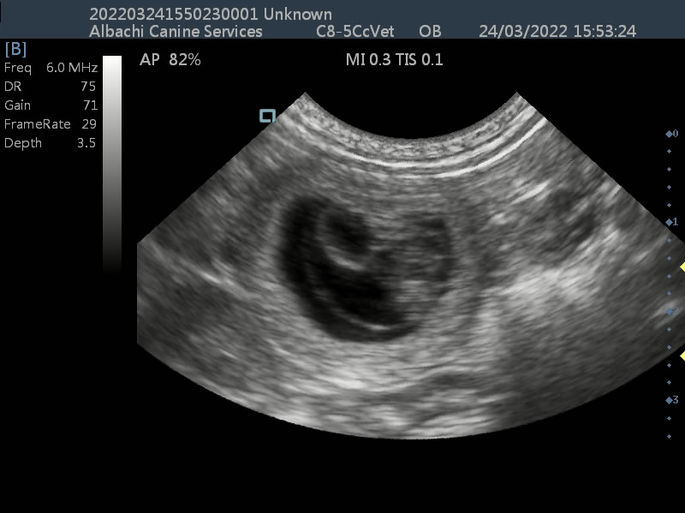

Secondary natal scan for Pomchi bitch to reconfirm delivery date and check progress of puppies.